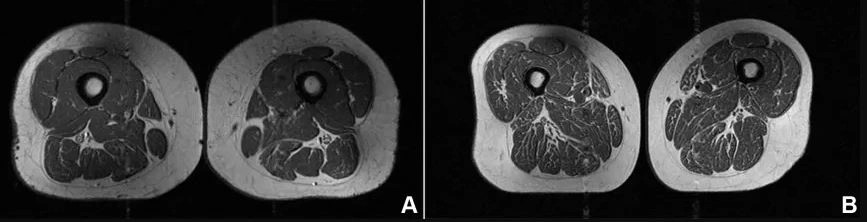

Një imazh nga rezonanca magnetike (MRI) tregoi kofshën e një gruaje 62-vjeçare që merrte rreth 87 për qind të kalorive nga ushqime shumë të përpunuara. Në vend të muskujve të fortë, skanimi zbuloi shtresa të shumta yndyre të shpërndara brenda dhe midis fibrave muskulore, ka shkruar CNN.

Sipas studimit të ri, prania e yndyrës brenda muskujve është një sinjal për probleme serioze shëndetësore, sidomos te personat që janë në rrezik për osteoarthritis të gjurit.

Lidhja mes yndyrës në muskuj dhe dhimbjes së gjurit është e fortë. Yndyra pengon rigjenerimin e fibrave muskulore dhe i dobëson ato, duke rritur rrezikun për osteoarthritis, forma më e zakonshme e sëmundjeve të nyjave që prek rreth 375 milionë njerëz në botë.

Studimi, i publikuar në revistën Radiology, ka analizuar 615 persona rreth moshës 60-vjeçare.

Rezultatet kanë treguar qartë se sa më shumë ushqime tё shumë përpunuara të konsumonte një person, aq më shumë yndyrë kishte në muskujt e kofshës, pavarësisht sasisë së kalorive.

“Gjatë gjithë studimit, sa më shumë ushqime shumë tё përpunuara konsumonte një person, aq më shumë yndyrë kishte në muskujt e kofshës, pavarësisht kalorive”, ka theksuar profesori Thomas Link.